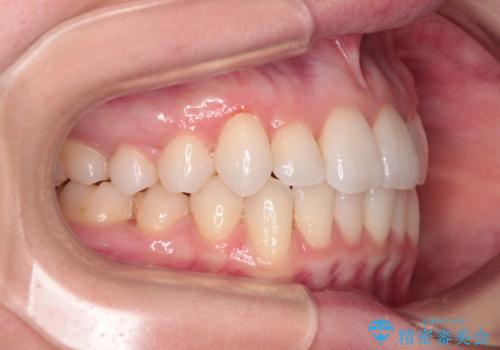

- 上下前歯のデコボコ、特に右上の八重歯を気にして来院された患者様です。

妊娠、出産の予定があり、毎月の通院が困難となる可能性があったため、インビザラインによる矯正治療を行うこととしました。

事前に親知らずを抜歯しておき、出産時期に困ることのないように準備をした上で治療を開始しました。

治療後半では悪阻によりマウスピースの装着時間が不十分となることもありましたが、それよりも前にしっかりと装着時間を守って治療を進めることができたため、特に気になるところなく治療を終えることができました。